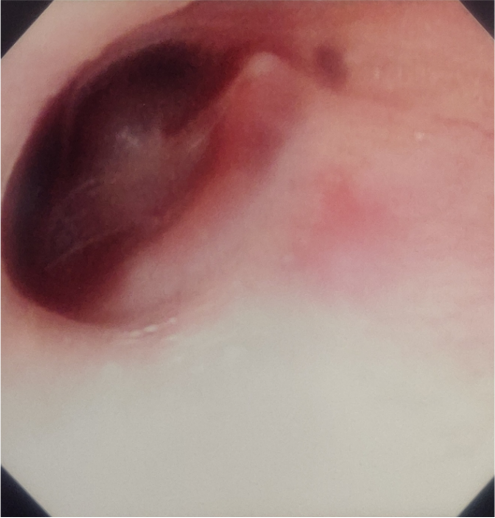

Caterina è una bambina di 9 anni giunta in Pronto Soccorso pediatrico per trauma cranico, procuratasi cadendo dal letto a castello (altezza stimata 1,8 metri) circa otto ore prima. La madre riferisce che la bambina avrebbe pianto subito dopo il trauma e che avrebbe avuto tre episodi di vomito, uno subito dopo l’evento e due a distanza di sei ore dal primo. All’ingresso in Pronto Soccorso i parametri vitali e l’obiettività neurologica sono nella norma. Si apprezza tuttavia un ematoma molle palpabile a livello dell’osso temporale sinistro e in otoscopia diretta si riscontra un emotimpano sinistro (Figura 1).

Dopo un trauma cranico, segni clinici quali otorrea, rinorrea, segno di Battle (ecchimosi retroauricolare), “Racoon eyes” (ecchimosi perioculare) ed emotimpano sono altamente predittivi di frattura della base cranica1. In particolare, il termine emotimpano indica la presenza di sangue nell’orecchio medio e di ecchimosi della membrana timpanica.